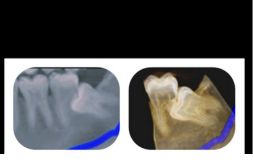

PROCEDURE FOR WISDOM TOOTH EXTRACTION

The tooth removal process depends upon the stage in which the wisdom teeth is. It is easy to extract wisdom tooth if it has fully erupted. But if the tooth is impacted then it will require an incision in the gums. Usually, the tooth is extracted in parts to minimize the amount of bone required to be extracted for tooth removal.